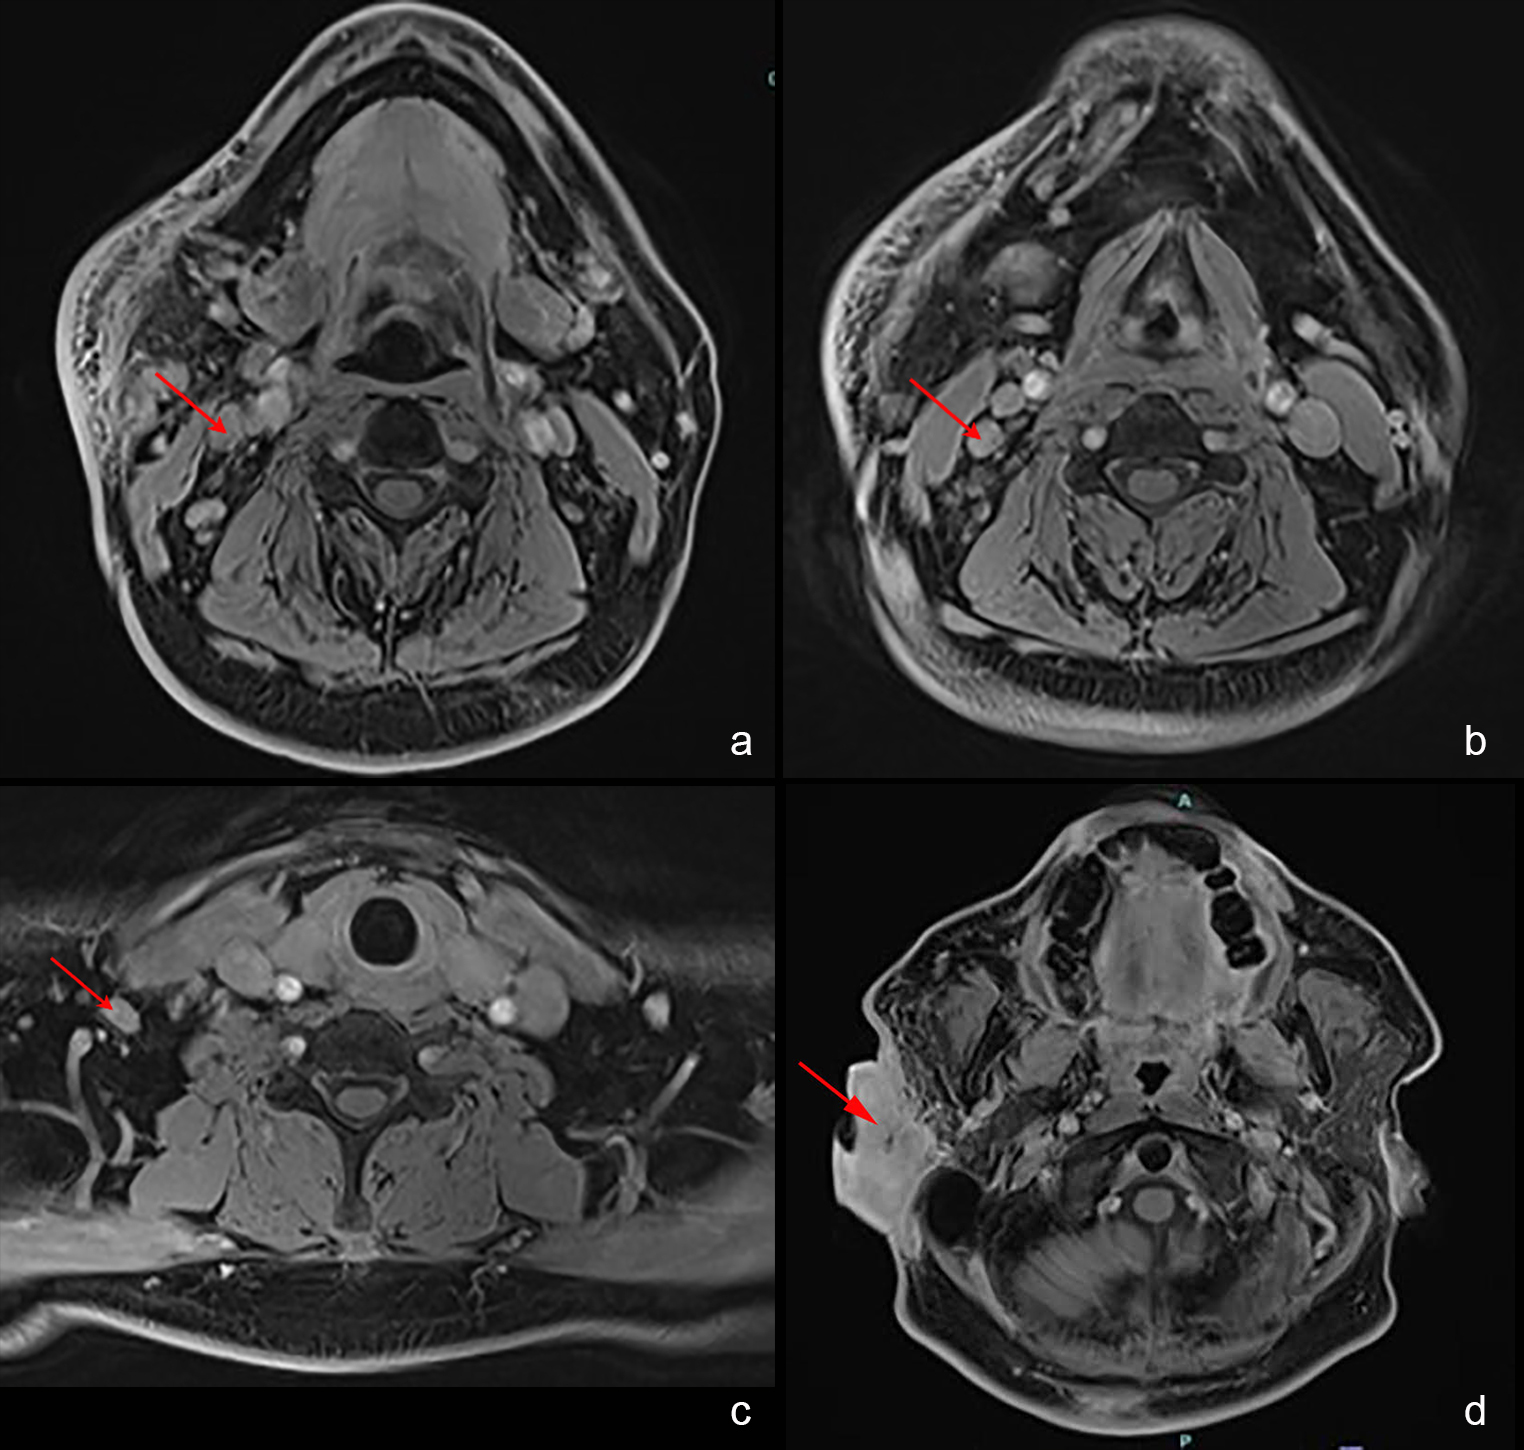

FIGURE 2: MRI images showed (a-c) enlarged and enhancing lymph nodes at levels 2, 3, and 4 of the right cervical neck regions; (d) lobulated soft tissue mass measuring 2.6 cm x 4.9 cm x 6.3 cm in the right pre- and postauricular space